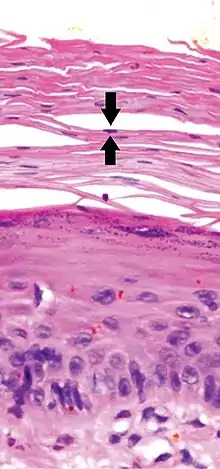

- a) Focal parakeratosis b,c) prominent parakeratosis

- In contrast, hyperkeratosis (pictured) may also show a heterogeneous stratum corneum, but a preserved granular layer is seen.